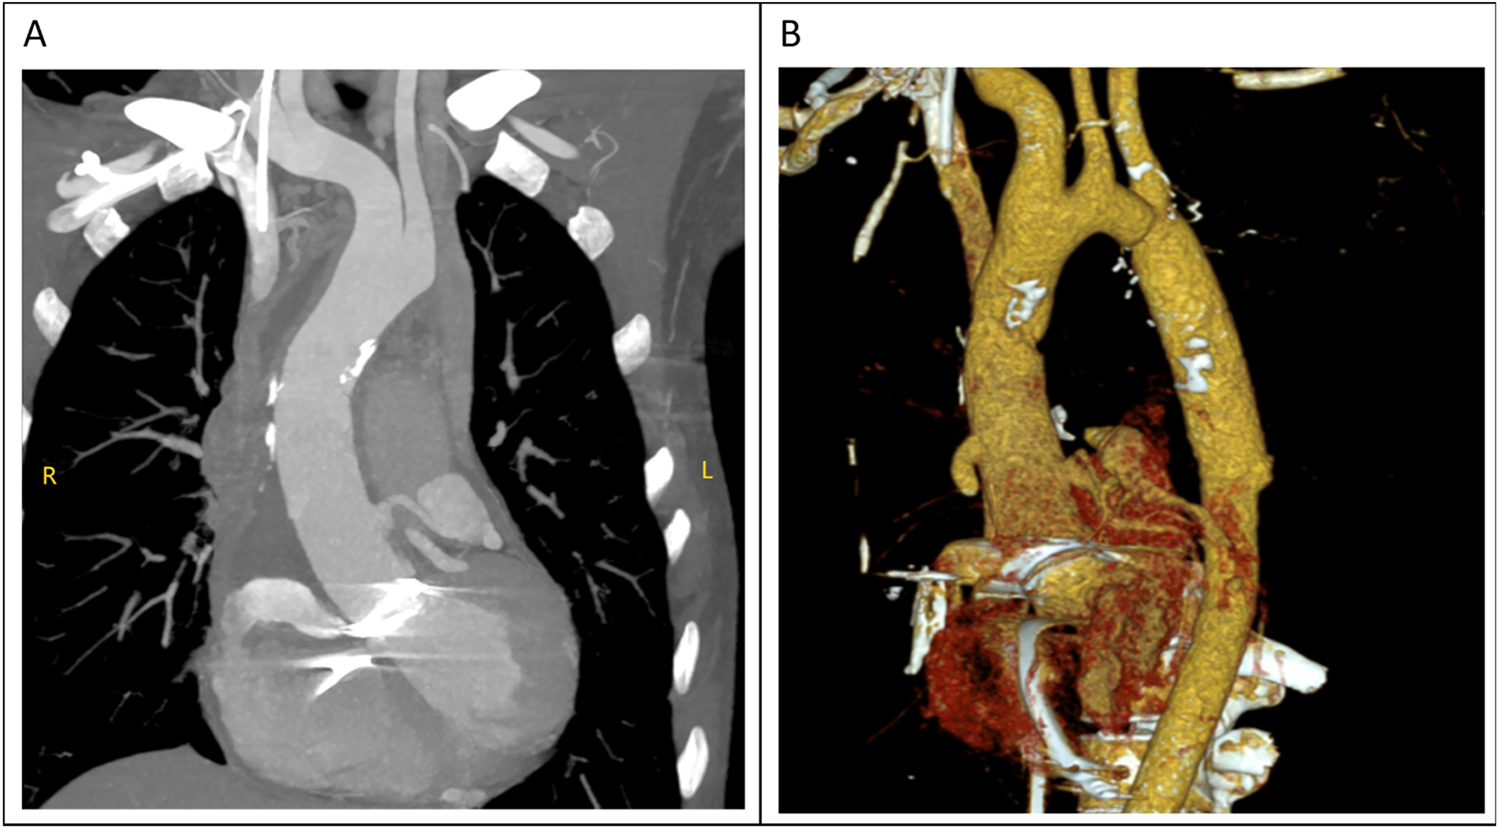

The total surgical time was 4 h and 25 min, with a cardiopulmonary bypass time of 143 min and an aortic cross-clamp time of 78 min. The tracheal tube was removed 13 h postoperatively. However, the patient began to experience frequent episodes of cardiac arrest lasting 5–10 s during the 20th and 25th hours postoperatively, for a total of 12 episodes, all of which reversed spontaneously. The cardiac conduction tissue was suspected to be damaged or affected by edema. An emergency temporary pacing device was implanted, and no further episodes of cardiac arrest occurred; her condition remained stable. Postoperative CTA scan showed satisfactory revision results (Figures 4A,B), and the postoperative echocardiogram demonstrated normal valve function. The patient was discharged on the ninth postoperative day.

Figure 4

(A,B) the diameter of the ascending aorta had returned to normal in the computed tomography (CT) examination performed after surgery.